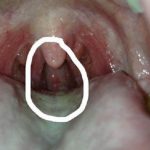

Как выглядит герпес в горле? Сыпь при данной инфекции имеет везикулярный характер. Чаще всего первоначально возникает герпес на губе, при инфицировании вирусом простого герпеса 1 типа. При попадании содержимого пузырьков в ротовую полость возбудитель заболевания проникает на слизистую оболочку горла и миндалин. Герпес в горле проявляется и общими воспалительными симптомами, которые наблюдаются при фарингите.

Патология развивается у людей с ослабленной иммунной системой. Герпес в горле у взрослых (см. фото 3) может возникнуть при инфицировании вирусом 1 или 2 типа (генитальный герпес). Итак, какие признаки указывают на герпес у взрослых в горле? При фарингоскопии отмечаются следующие явления: на слизистой оболочке горла визуализируются мелкие пузырьки с прозрачным содержимым. Местами герпес на горле сливается, и образуются крупные везикулы.

Часть пузырьков вскрывается, в результате образуются участки эрозий. При заживлении герпес горла проявляется возникновением корочек. При вскрытии везикул, патологическая жидкость распространяется. Вследствие этого может появиться герпес во рту у взрослых, который имеет те же проявления. Герпес в горле у взрослых часто сопровождается повышением температуры тела и болью при глотании.